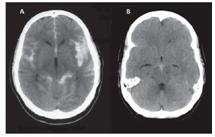

【108-2 醫學(四) 第46題】李小姐,55歲,因突發性頭痛及癲癇發作、意識障礙被同事送到急診室,其電腦斷層攝影檢查(CT)如下圖。下列敘述何者錯誤?